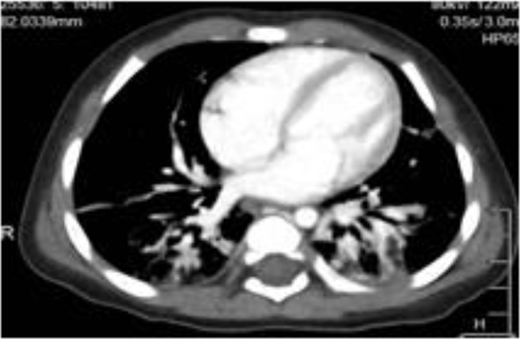

Dihydrorhodamine (DHR) test in patient 7, patient 8, and a healthy control.